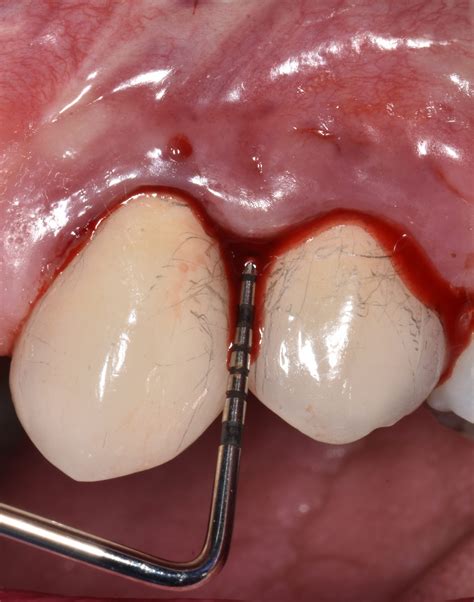

Periodontal probing areas – Artofit

Periodontal probing areas – Artofit